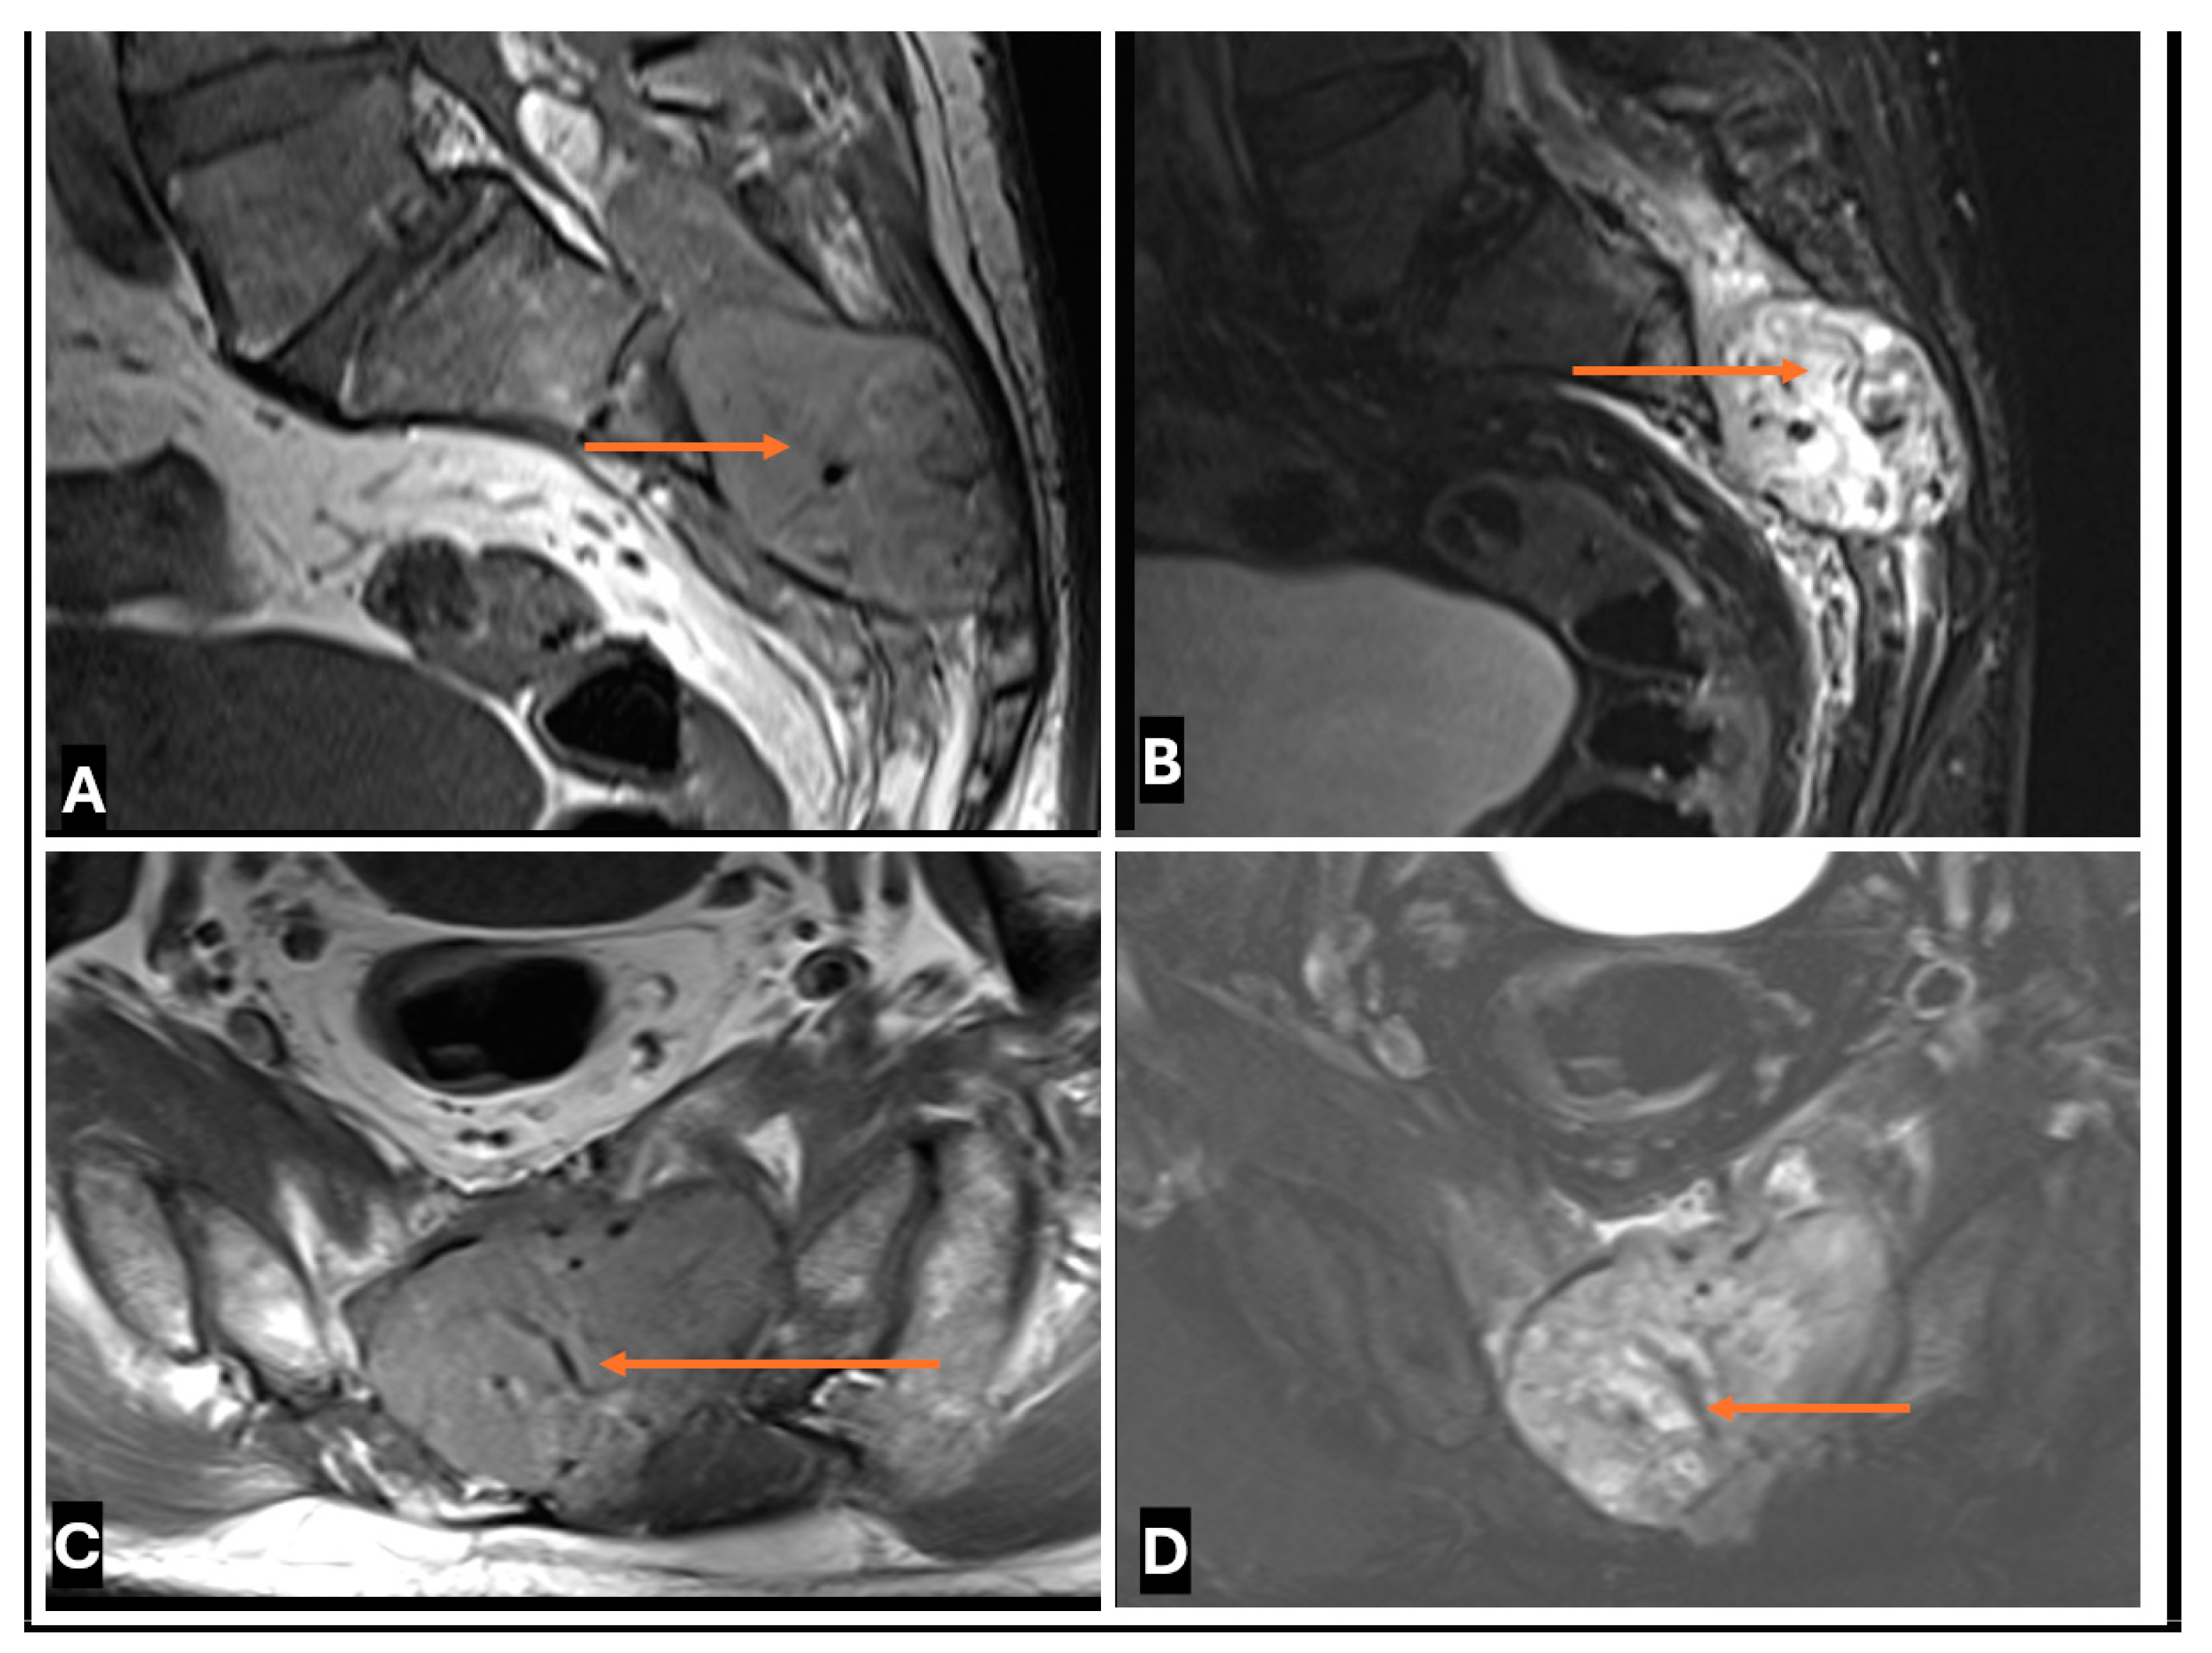

- Primary Sarcomas: Soft-tissue sarcomas are uncommon, accounting for just over 1% of adult malignancies. Synovial sarcoma, clear cell sarcoma, and epithelioid sarcomas are known to involve peripheral nerves. CT/MR reveals a large soft tissue mass with areas of necrosis or calcification and heterogeneous contrast enhancement. F-18 FDG uptake is useful for both tumor staging and treatment assessment (Figure 26, Figure 27 and Figure 28).